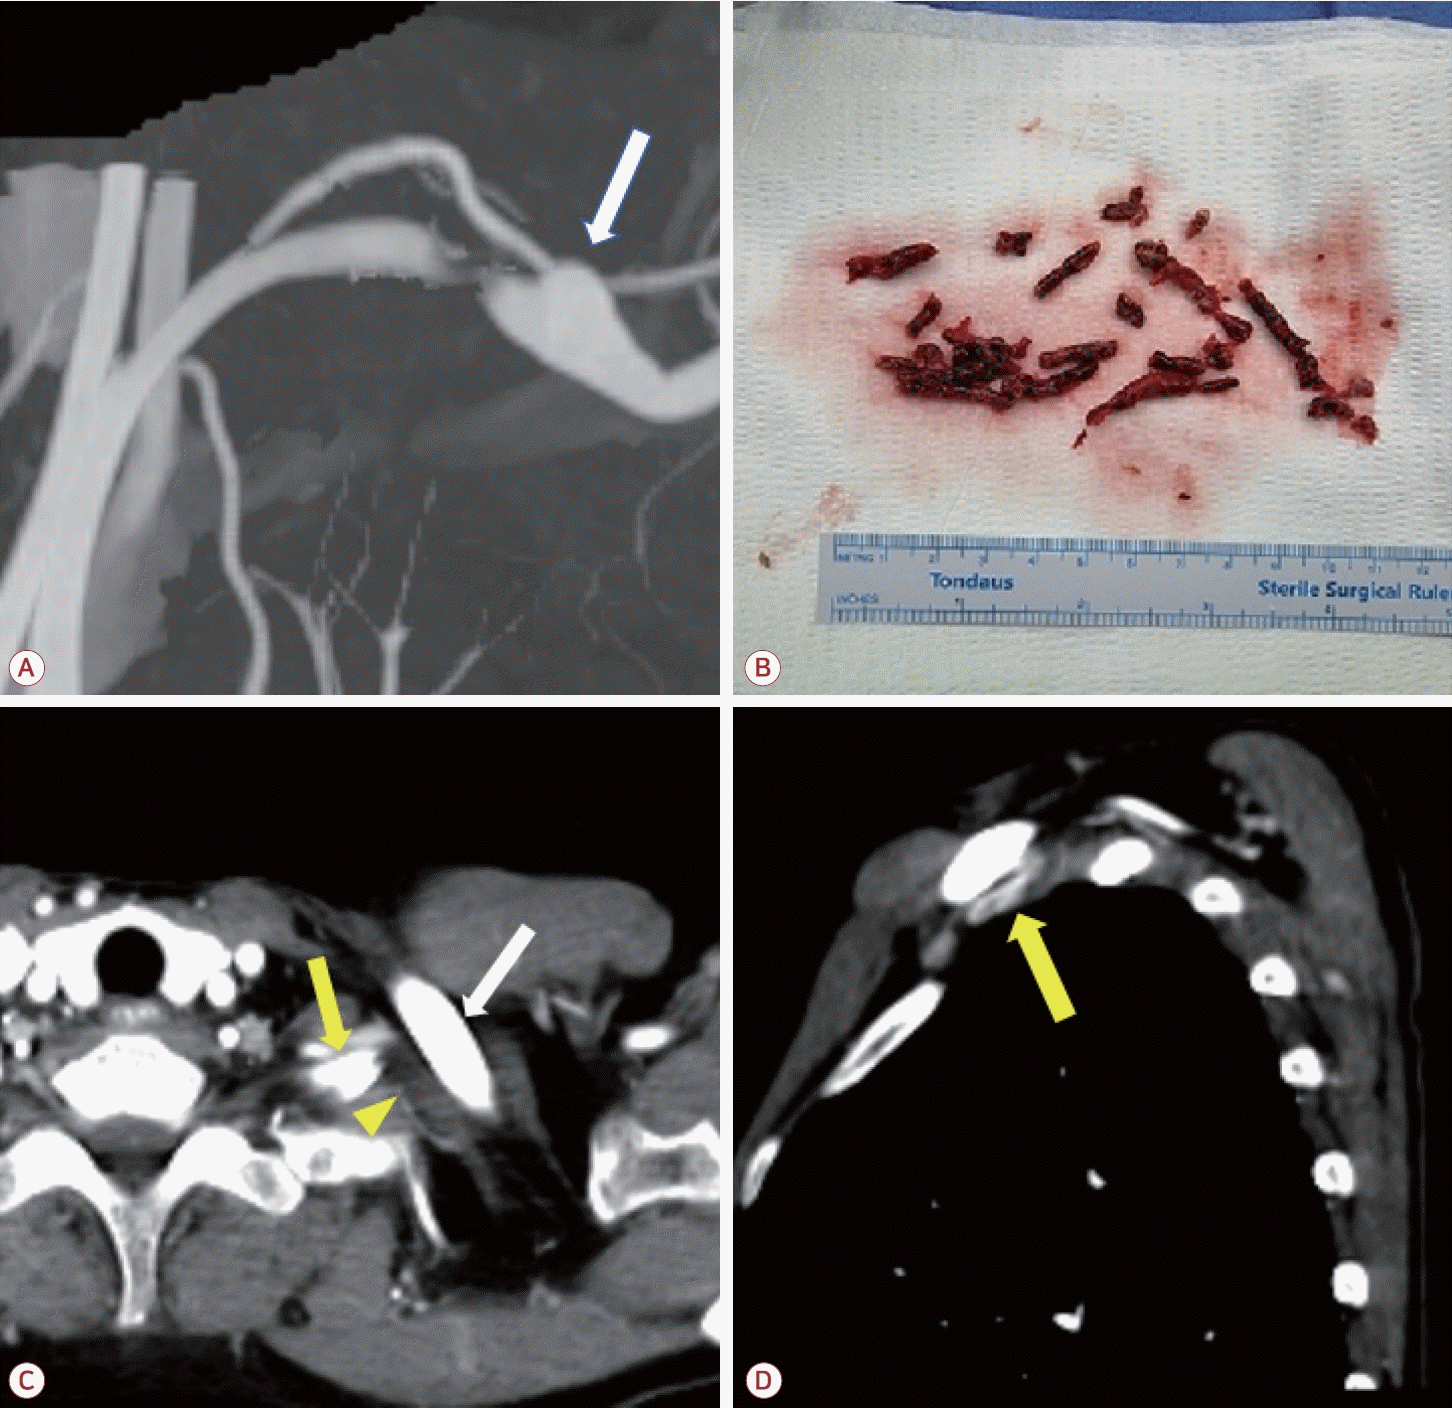

Figure 1.

Magnetic resonance imaging and computed tomographic angiography on admission. (A) Diffusion weighted imaging showing acute multiple embolic infarctions of the right cerebellum, cerebellar peduncle, and left posterior lobe. (B) Intracranial computed tomography (CT) angiography. No remarkable abnormal findings except hypoplastic right vertebral artery. (C) Reconstruction of upper extremity CT angiography on the second day of admission showing occlusion of the left brachial artery just after the origin of the left vertebral artery (yellow arrow). (D, E) Sagittal view of upper extremity CT showing the subclavian artery. Luminal narrowing with absent blood flow and thrombosis on the left side versus patent artery (red arrow) between the clavicle and accessory rib on the right side (white arrow).

특이 질환이 없는 58세 여자가 내원 19시간 전 발생한 어지러움 및 이명을 주소로 응급실에 내원하였다. 1달 전부터 왼팔이 간헐적으로 저린 증상이 있었다. 내원 당시 활력징후에서 우측 상지의 혈압은 140/70 mmHg로 측정되었으나 좌측 상지의 혈압은 측정되지 않았다. 또한 맥박 64회/분, 호흡 16회/분, 체온 36.0℃로 측정되었다. 시행한 신경계 진찰상 우측 상하지의 실조 증상이 관찰되었으며 근력 약화 및 감각 증상은 확인되지 않았고 NIH뇌졸중척도(National Institutes of Health stroke scale) 2점이었다. 병적 반사나 안진 등은 뚜렷하지 않았다. 좌측 상지에서는 맥박이 측정되지 않았고 청색증이 관찰되었다.뇌자기공명영상의 확산강조영상(diffusion-weighted image) 에서는 우측 소뇌 및 소뇌다리, 좌측 후두엽에서 다발색전 양상의 고신호강도 병변이 보였다(Fig. 1-A). 또한 이후 시행한 뇌전산화단층촬영 혈관조영영상에서는 우측 척추동맥의 형성 저하 외에는 뇌내혈관 및 경동맥의 유의미한 협착은 관찰되지 않았다(Fig. 1-B). 또한 상지 전산화단층촬영혈관조영에서 쇄골하동맥의 폐색이 관찰되었으며(Fig. 1-C) 우측에 비해 좌측 쇄골과 경추늑골 사이 공간이 협소하고 혈류가 감소한 소견이 보였다(Fig 1-D, E). 혈액 검사상 D-이합체(D-dimer)는 3.21 μg/mL (정상, 0.0-0.5)로 상승되어 있었으며 항인지질인자, C/S단백질(protein C/S), 항트롬빈-III, 폰빌레브란트인자 등의 검사는 별도로 진행하지 않았다. 심전도, 경흉부 및 경식도심초음파, 24시간심전도 검사에서 심인성 색전증을 일으킬 수 있는 다른 질환은 발견되지 않았다.환자는 좌측 쇄골하동맥 폐색 및 동반된 뇌경색에 대해 입원하여 저분자량헤파린인 에녹사파린(enoxaparin) 1 mg/kg 하루 두 번으로 항응고 치료를 시작하였고 입원 3일차에 쇄골하동맥의 혈전색전제거술(thromboembolectomy)을 시행하였다(Fig. 2-B). 시술 후에 환자는 추가적인 뇌경색 병변이 발견되지 않았고 좌측 상지의 청색증이 호전되었으며 혈압 또한 우측과 차이를 보이지 않았다. 이후 에픽사반(apixaban) 5 mg 하루 두 번으로 약물 교체 이후 퇴원하였다. 시술 3개월 이후 추적 관찰한 혈관조영에서 이전에 보였던 혈전은 모두 제거되었고 새로운 혈전이 발생하지 않았음을 확인하였다. 또한 좌측 경추 늑골과 쇄골에 의한 쇄골하동맥의 압박 소견 및 이로 인한 말초 동맥류가 관찰되었다(Fig. 2-A, C, D). 이에 환자는 aTOS로 인한 뇌경색으로 최종 진단할 수 있었다. 환자는 항혈소판제인 아스피린 하루 100 mg으로 약물을 교체하였다. 환자에게 흉곽 출구증후군에 대해 경추늑골제거술 및 혈관성형술 등 수술적 치료를 권유하였으나 거절하여 약물 복용 유지 중에 있다.본 증례 보고에 대하여 고려대학교구로병원 의학연구심의위원회의 승인을 받았다(IRB No. 2025GR0163).